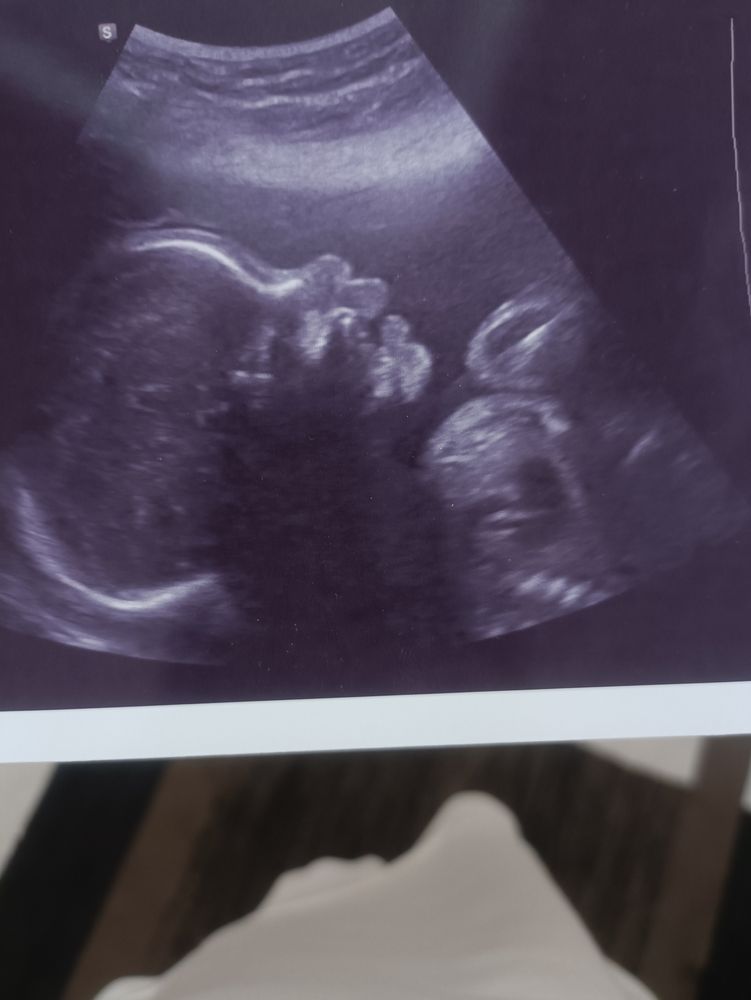

Год после переноса эмбриона 4ab💫

Я стала МАМОЙ !Год назад была в отчаянии, даже не надеялась на удачу. Так как первый перенос был пролётным. После первого переноса следующий цикл не получилось сделать перенос, были всякие препятствия. Тогда я просто доверилась вселенной, и отпустила ситуацию. Будь как будет, если суждено, то ничего не помешает стать мамой, если нет значит такова судьба...

Итог: Карапузу 3,5 месяца. Тест показал призрак на 3дпп.